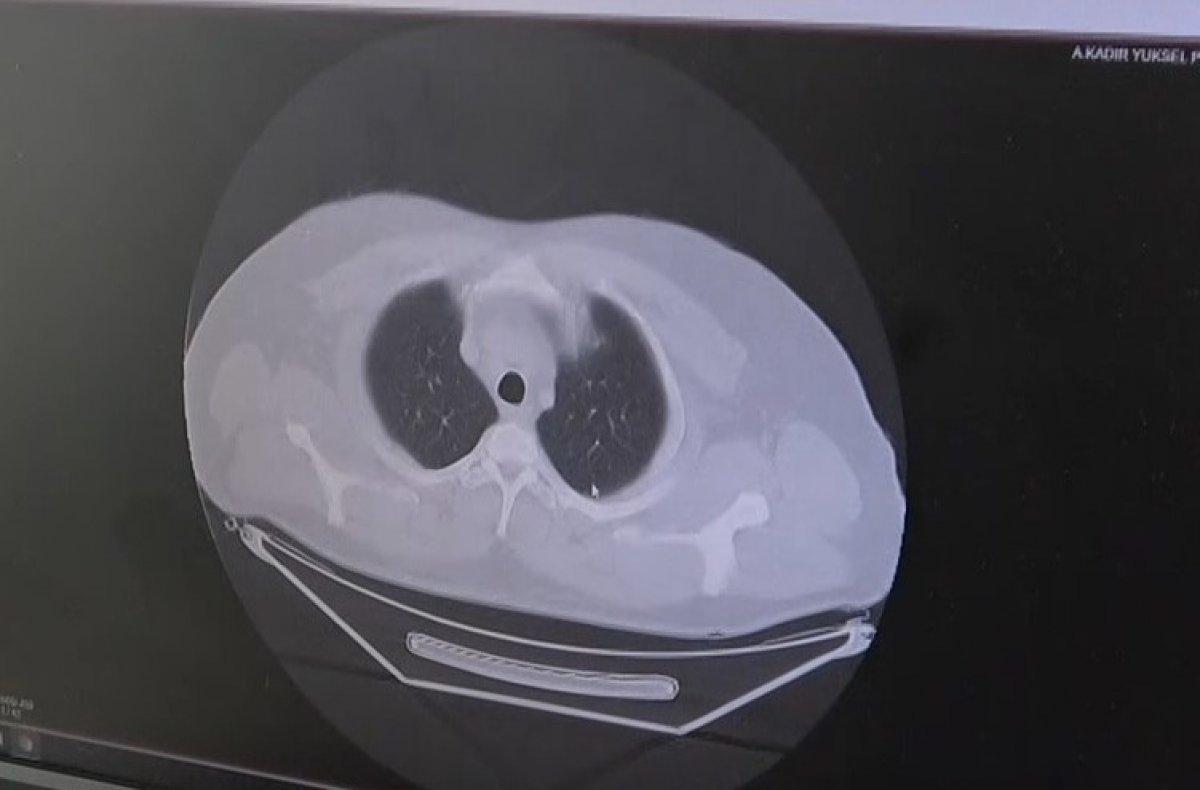

Koronavirüsün bulaşmasından sonra 3 gün içinde hızla akciğere nasıl yayıldığını gösteren grafikleri gösteren Dr. Demir, hastanede yoğun bakımda yatış yapanların çoğunluğunun delta varyantı olduğunu söyledi.